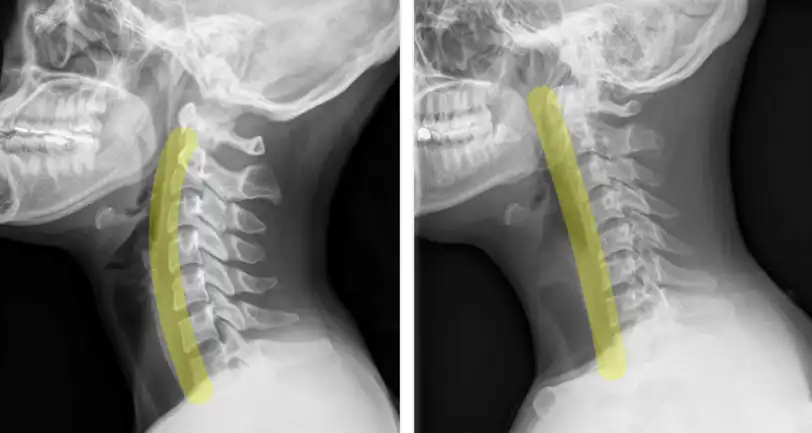

일자목이란 목 디스크가 손상되면서 경추 전만이 소실되어 목뼈들이 일직선이 된 상태를 말합니다.

정상적인 목을 엑스레이 사진으로 보면 앞으로 완만하게 휘어지는 정상적인 곡선을 가지게 됩니다. 목의 정상적인 곡선은 신생아가 고개를 가누기 시작할 때부터 생기며 이를 경추 전만이라고 부릅니다.

가장 자연스럽고 정상적인 정렬 상태인데요. 이런 자연스러운 경추 전만이 있어야 머리의 무게가 목뼈의 중심을 지나게 되면서 목 디스크에 걸리는 압력을 줄여주게 되는 것이죠.

목 디스크가 손상되어 일자목이 되면 목의 움직임은 30%가량 줄어들고 목 디스크에 걸리는 압력이 많게는 90%까지 증가합니다.